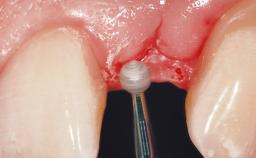

Immediate Flapless Placement of an Implant in a Maxillary Left Central Incisor Site

A 29-year-old female patient presented for treatment to replace the upper left central incisor tooth with an implant- supported restoration. The tooth had been intermittently symptomatic for the previous 12 months. The tooth had originally suffered trauma about 15 years previously. Several endodontic treatments had been performed, including an apicectomy procedure to retain the tooth. The patient was healthy and a non-smoker. She had reasonable expectations in regard to esthetic outcomes and the risk of marginal tissue recession following treatment. At medium smile, the gingival margins of the upper teeth were visible, with a display of 3 to 4 mm of the gingival margins. Gingival recession of tooth 21 and a discrepancy in the gingival levels between teeth 11 and 21 was observable during normal speech and smile.

| Placement Protocol | Immediate implant placement |

| Tooth Site | Maxillary incisor or canine |

| Socket Morphology | Single-root socket |

| Socket Integrity | Damage to one or more bone walls |